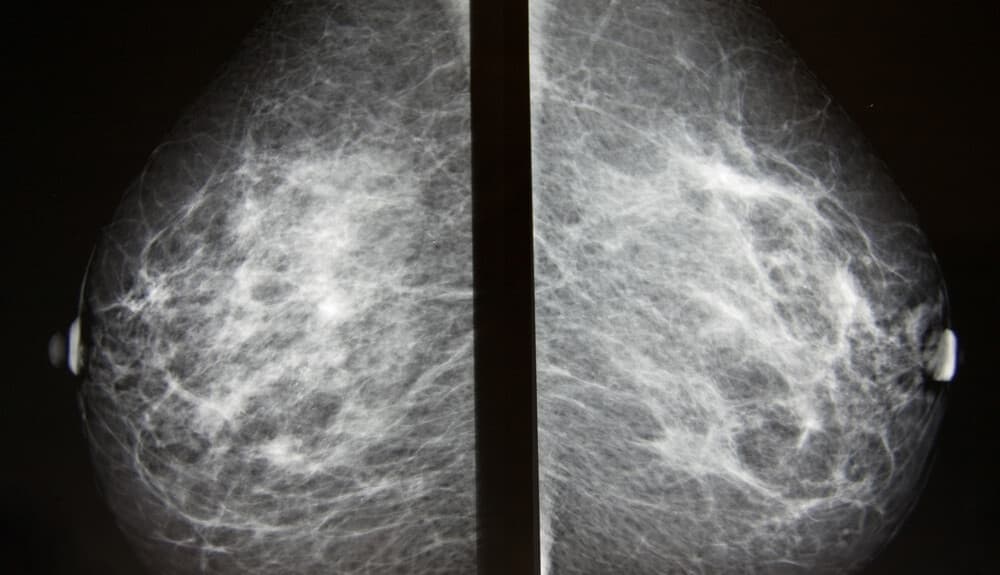

Bei der Mammographie werden Röntgenaufnahmen der Brüste angefertigt. Diese dienen entweder dem Brustkrebsscreening oder diagnostischen Zwecken, zum Beispiel zur Abklärung bestimmter Symptome oder auffälliger Befunde aus anderen bildgebenden Verfahren.

Während der Aufnahme wird die Brust zwischen zwei festen Flächen komprimiert, damit das Brustgewebe sich entfalten lässt. Anschließend entstehen schwarz-weiße Röntgenbilder, die auf einem Computerbildschirm angezeigt und auf Anzeichen für bösartige Veränderungen untersucht werden. Die Aufnahmen werden mit einem speziell für Mammographien entwickelten Röntgengerät gemacht. Zur Erzielung guter Bildqualität und zur Minimierung der Strahlenbelastung werden die Brüste einzeln mithilfe spezieller Kunststoffplatten zusammengedrückt, und es werden jeweils zweidimensionale Aufnahmen aus zwei Richtungen erstellt. Die konventionelle Mammographie ist in der Regel nicht schmerzhaft, das Zusammendrücken der Brüste kann jedoch unangenehm sein. Eine Technikerin oder ein Techniker hilft dabei, Kopf, Arme und Rumpf so zu positionieren, dass das Gerät die Brust ungehindert erfassen kann.

Wie bereits erwähnt, entstehen bei der Mammographie schwarz-weiße Aufnahmen des Brustgewebes. Diese sind digitale Bilder, die auf einem Computerbildschirm angezeigt und vom Radiologen analysiert werden.

Der Radiologe sucht nach Hinweisen auf bösartige Veränderungen und nach anderen Zuständen, die weitere Untersuchungen, Beobachtung oder Behandlung erforderlich machen könnten.